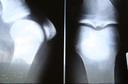

O diagnóstico12 do “reumatismo” ou doença reumática é eminentemente13 clínico, dependente da história médica dos pacientes. Os exames de imagem podem confirmar o diagnóstico12 depois que a doença está bem evoluída. Um diagnóstico12 diferencial deve ser feito com grande parte das pessoas que sofrem diminuição da flexibilidade e dores nas articulações3, sem que isso seja “reumatismo” ou qualquer outra doença inflamatória.